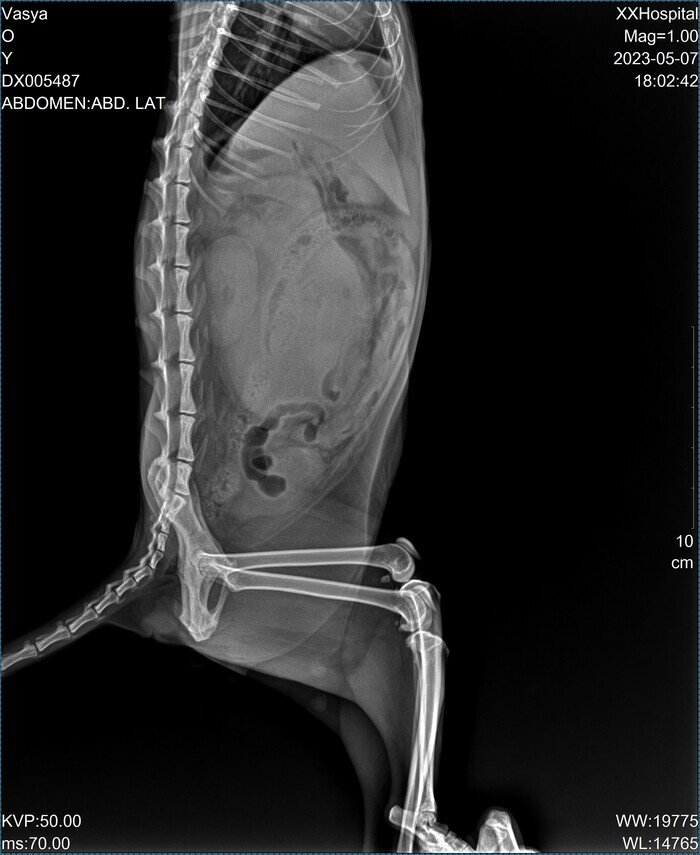

Сегодня моего кота приезжал посмотреть знакомый ветврач и с казал что его надо срочно везти в ветклинику и делать ему рентген в боковой проекции и анализы крови. Сказал что у него правая почка увеличена в размерах раз в пять. Предположительный диагноз: Гидронефроз почки? Отвез на рентген. Вот два снимка которые сегодня ему сделали. Рентгенолог говорит что на снимках она ничего не видит, кроме того что правая почка сильно увеличена в размере и ему надо делать еще и узи! В этой клинике где я был сегодня узи нет. Сделали ему общий анализ крови и анализ на биохимию. Результаты анализов крови будут готовы только завтра вечером. Говорит, рентгенолог что, скорее всего, проблему у кота придется решать только хирургическим путем и эта операция может стоить от 100 тыс. руб. Гарантий при этом совсем никаких нет! Кому-нибудь приходилось лечить похожее у котов или кошек? ЗЫ. Коту примерно 2, 5 года (точно не знаю так как взял его уже почти взрослым с улицы). У меня он живет полтора года. ЗЫ. ЗЫ. На

Отвез на рентген. Вот два снимка которые сегодня ему сделали.

Рентгенолог говорит что на снимках она ничего не видит, кроме того что правая почка сильно увеличена в размере и ему надо делать еще и узи! В этой клинике где я был сегодня узи нет.